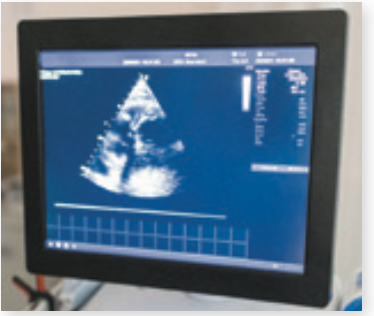

A stiff, calcified aortic valve limits the amount of oxygenated blood the heart delivers to organs throughout the body. Left untreated, this condition—called aortic stenosis—can eventually be deadly. Fortunately, a damaged aortic valve can be replaced in a surgical or catheter-based procedure.